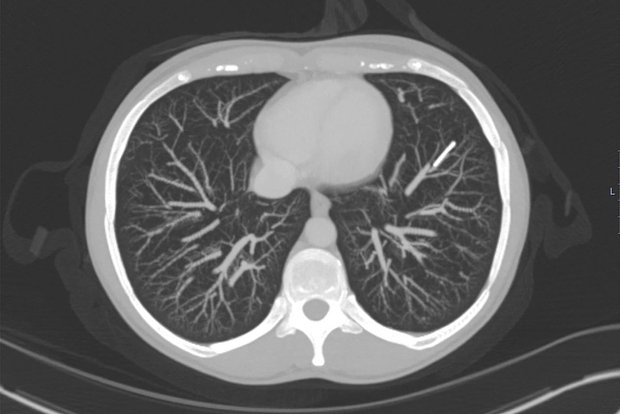

Спустя годы женщина решила удалить имплантат, но врачи не обнаружили его в руке. После серии исследований, включая рентген и КТ с контрастом, устройство нашли в артерии левого легкого — оно переместилось через венозную систему и сердце. Интересно, что за все время у пациентки не возникло ни кашля, ни боли, ни других симптомов, связанных с миграцией.